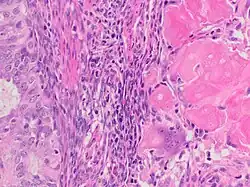

Endometrial adenocarcinoma with necrotic ghost cells of keratinocytes at right in image, leaving pink keratin and clear spaces at the prior locations of the nuclei.

A ghost cell is an enlarged eosinophilic epithelial cell with eosinophilic cytoplasm but without a nucleus. It has lost its nucleus and cytoplasmic contents, leaving behind only the cell membrane and sometimes remnants of the cell's structure. In pathology, ghost cells are often associated with certain types of tumors, such as pilomatricomas and calcifying odontogenic cysts, where they appear as pale, anucleate cells that have undergone degeneration or calcification.

The ghost cells indicate coagulative necrosis where there is cell death but retainment of cellular architecture. In histologic sections ghost cells are those which appear as shadow cells. They are dead cells. For example, in peripheral blood smear preparations, the RBCs are lysed and appear as ghost cells.